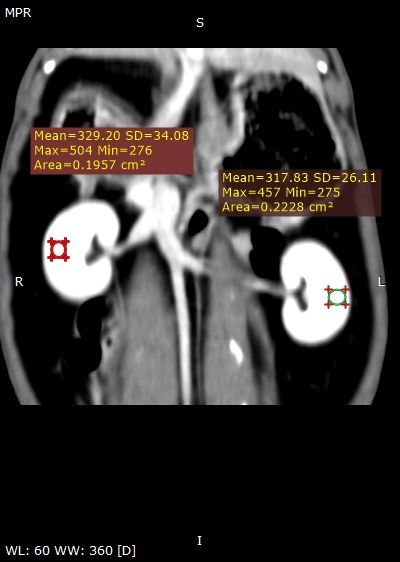

Le diagnostic se fait par échographie et certains cas peuvent nécessiter un scanner particulier pour vérifier la fonction du rein. Les traitements sont variés. Un traitement médical en hospitalisation peut être intenté, sinon une chirurgie voire l'implantation d'une prothèse (subcutaneous ureteral bypass) peut être proposée. Dans des cas extrêmes, il peut être recommandé de retirer le rein (néphrectomie).